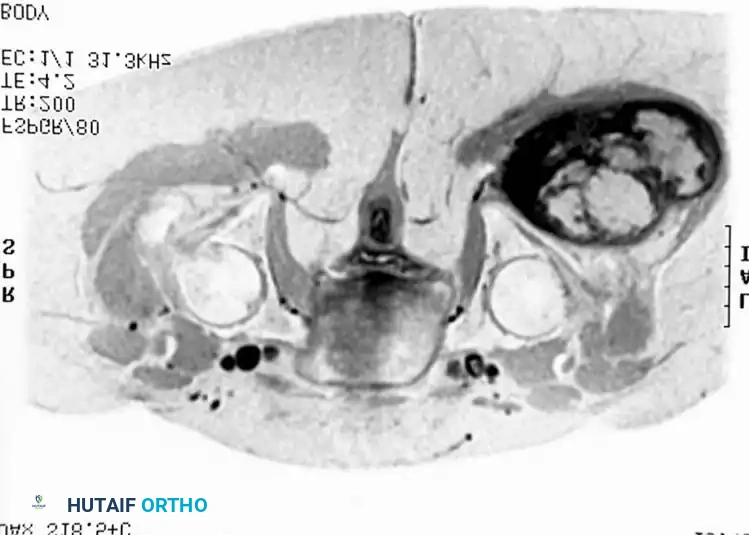

Imaging:

MRI is highly specific for well-differentiated variants, demonstrating fat signal intensity (bright on T1, suppresses on STIR/Fat-Sat) with thick, nodular septations.

T1-weighted MRI of a well-differentiated liposarcoma (atypical lipoma) of the thigh.

Contrast-enhanced, fat-suppressed axial MRI of the same lesion. Note the multiple thick, enhancing septa distinguishing it from a benign lipoma.